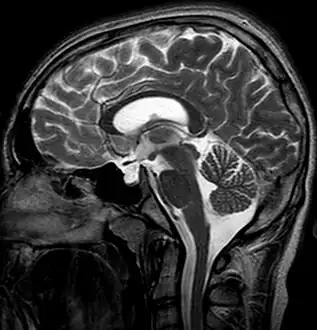

-

Empty sella- MRI Scan of the brain, sagittal T2-weighted -

Empty sella in MRI

The diagnosis of empty sella syndrome, done via examination (and test), may be linked to early onset of puberty, growth hormone deficiency, or pituitary gland dysfunction (at an early age).[2] Additionally there is: